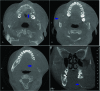

Figure 2

Cone beam computer tomography scan of maxillofacial bone. A, Axial section showing an osteolytic lesion of the left maxillary (arrow). B, Axial section showing an osteolytic lesion with bucco-lingually bone expanding of the right mandible (arrow). C, Axial section showing an osteolytic lesion with bucco-lingually bone expanding of the left mandible (arrow). D, Coronal section showing bucco-lingually bone expanding of the mandible and tooth displacement (arrow).